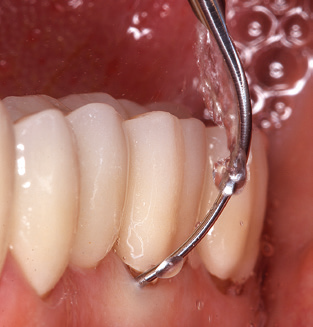

Fig. 1: Panoramic radiograph of initial situation in 2004.

A 52-year-old patient presented in our clinic for the first time in 2004 following tooth loss in the third quadrant, expressing a desire for a new prosthetic restoration. Periodontal and radiological diagnostics revealed the need for extensive periodontological treatment. In addition, teeth 48, 28 and 27 were attributed a very poor prognosis and were subsequently extracted (Fig. 1). Following the successfully completed, systematic periodontological treatment, a fixed dental implant was inserted with the introduction of five implants in tooth regions 35, 36, 37, 46 and 47. Prosthetic treatment of the natural teeth was effected with veneered zirconium dioxide ceramic crowns; the implants were composed of two-piece, individual zirconium dioxide abutments and similarly veneered crowns made of a zirconium dioxide ceramic (Cercon base colored, Dentsply Sirona Lab). Definitive insertion of the prosthetic restoration occurred in 2005.